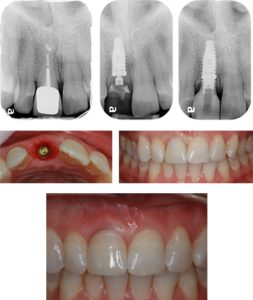

Prosthodontics Department :

• Crown (cap) for broken tooth.

• Bridge (fixed prosthesis) for missing tooth.

• Flexible denture (Removable prosthesis) for missing teeth.

• FlexibleDental implant.

• Maxillofacial prosthesis for post- surgical rehabilitation.

• Prosthesis for cist lip & palate.